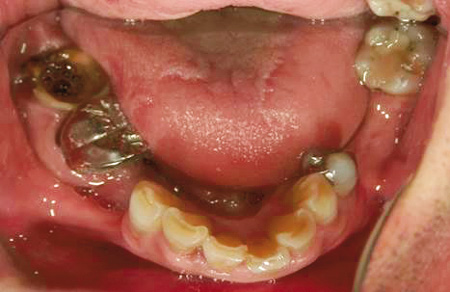

40代男性。右上と左下の歯が喪失して、そのままになっている。

左上と右下の歯は治療途中で崩壊しており、このまま治療中断を繰り返せば歯を喪失することが予想される。